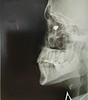

– На момент поступления глаз имел вид сдутого шарика, а острота зрения снизилась до 1%. Для уточнения диагноза мы выполнили рентген-диагностику. Она позволила определить локализацию инородного тела и составить план операции, - рассказал Петр Чернядьев.